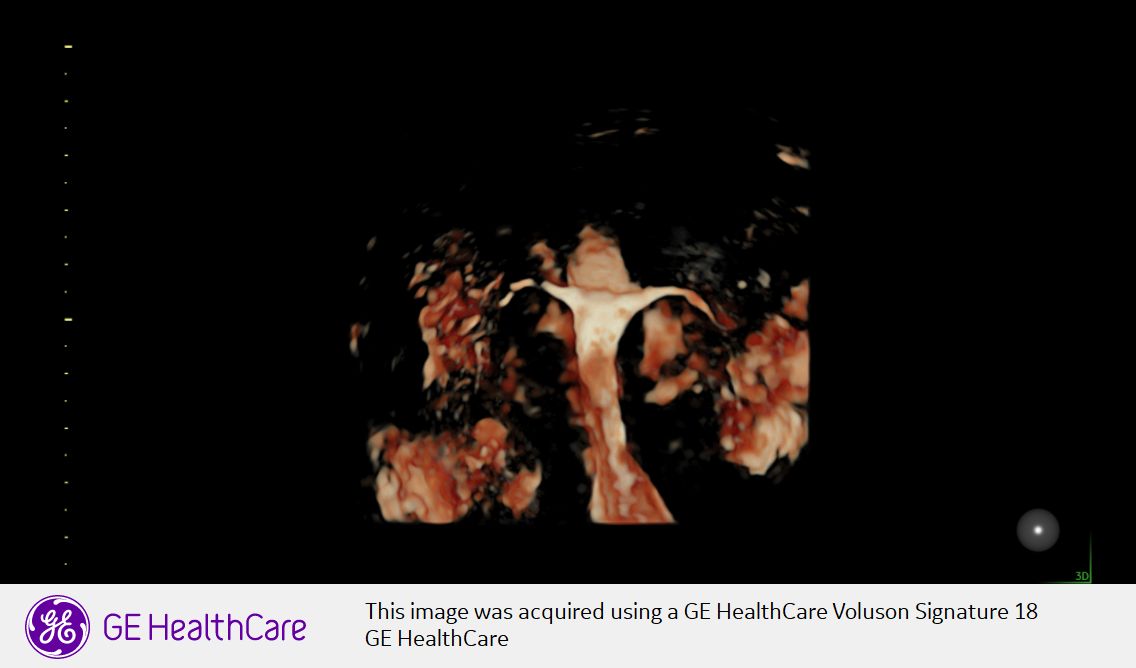

Sono Domenico Incandela, specialista in Ginecologia e Ostetricia e Fisiopatologia della Riproduzione. Sono Dirigente Medico I liv. con incarico di Alta specializzazione in diagnosi e cura dell'Endometriosi presso l'ARNAS Ospedale Civico di Palermo dove sono responsabile del Servizio di Isteroscopia e dell' Ambulatorio di Endometriosi presso il Centro di riferimento regionale per l'Endometriosi . Sin dall'inizio della mia attività mi sono occupato di gravidanza e diagnosi prenatale, negli anni ho curato la pratica e lo studio dell'endoscopia ginecologica (Laparoscopia e Isteroscopia) e della diagnosi e cura dell'Endometriosi . Presso il mio studio viene posta grande attenzione a ciò che concerne l'assistenza alla donna in gravidanza e successivamente in puerperio In tal senso è presente un Pelvic Center volto alla riabilitazione del pavimento pelvico attraverso l'ausilio di apparecchiature a radiofrequenza , sia in fase pre e post partum, in donne con atrofia vulvo-vaginale in menopausa o con condizioni di vulvodinia e dispareunia in genere, condizione molto frequente anche nella paziente affetta da endometriosi. Mi avvalgo inoltre dell'utilizzo dell'ozonoterapia strumento fondamentale per il trattamento di infezioni vagino\urinarie ricorrenti, infezioni virali quali l'HPV o condizioni di atrofia vulvo-vaginale menopausa correlate.

• Chirurgia endoscopica ginecologica

Presso il mio studio mi occupo di Ostetricia monitorando la gravidanza fisiologica e a rischio avvalendomi di tecniche di diagnosi prenatale (ultrascreening, ecografia morfologica, ecografia di accrescimento, cardiotocografia)mi avvalgo della collaborazione di un'Ostetrica, la Dott.ssa Giorgia Ranieri per ciò che concerne l'assistenza alla donna in gravidanza e successivamente in puerperio.

Per ciò che concerne la ginecologia mi occupo di diagnosi e cura dell'endometriosi, diagnosi e cura della patologia cervicale con l'esecuzione di colposcopia ,tamponi cervicali e buccali per HPV, trattamento di tutte le patologie uterine effettuando presso il mio studio isteroscopie office, consulenze contraccettive e per infertilità di coppia . Collabora con me una psicologa, la Dott.ssa Arianna Mellina, per il supporto alle problematiche di coppia di natura sessuale, il supporto alla paziente con vaginismo e vulvodinia, alla paziente con Endometriosi